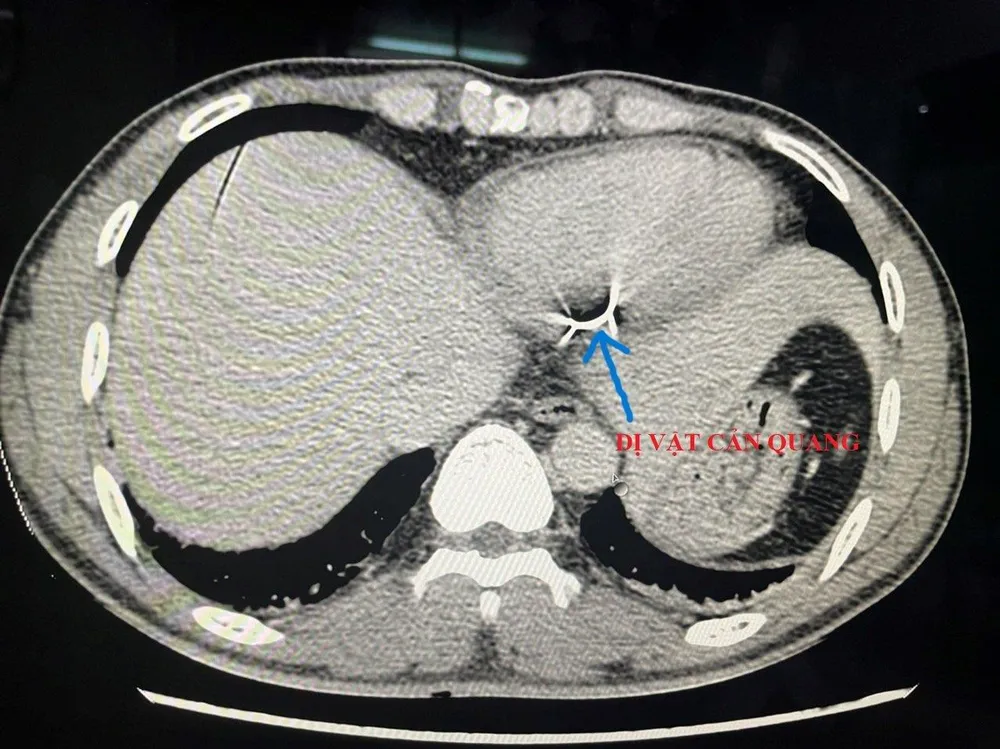

Hình ảnh chụp cắt lớp phát hiện dị vật trong tim bệnh nhân. Ảnh: BVCC |

Kết quả X-quang ngực - tim - phổi - thẳng, siêu âm tim màu, chụp cắt lớp cho thấy có 1 dị vật nằm dọc thành sau thất trái và có thông vào buồng tim. Bệnh nhân ngay lập tức được chỉ định phẫu thuật cấp cứu.